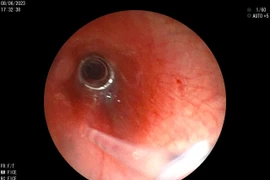

Các bác sĩ khoa Tai Mũi Họng – Bệnh viện Sản Nhi Nghệ An cho biết, khoa vừa tiến hành nội soi gắp dị vật là một cục pin nhỏ ra khỏi đường thở cho một bệnh nhi 8 tháng tuổi.